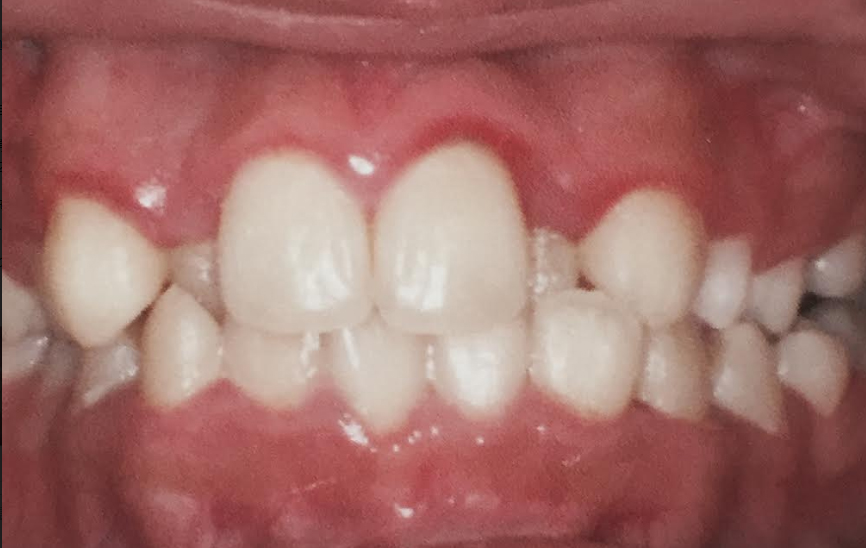

写真だけで正確な咬み合わせを判断するのは難しいですが、前歯は横幅(サイズ)が大きい様に見えます。歯が大きいために前歯が押し合って、いわゆる叢生(乱杭歯)の状態になっています。

あなたの希望が、前歯がうまく並べば満足出来るなら前歯だけの部分矯正で治すことは可能と思われます。いずれにしても、気になる治したい部分の矯正を優先的に考えるべきでしょう。

部分矯正で前歯だけ矯正する場合は、抜歯する必要は有りませんが、一般的には大きな前歯を選択して、小さくする(0.4~0.8

mm程)必要があります。もちろん、痛くない範囲で削ります。

前歯だけの部分矯正で治せれば、歯を動かす期間は1年以内、もちろん外から見えない裏側(舌側)矯正で矯正可能です。